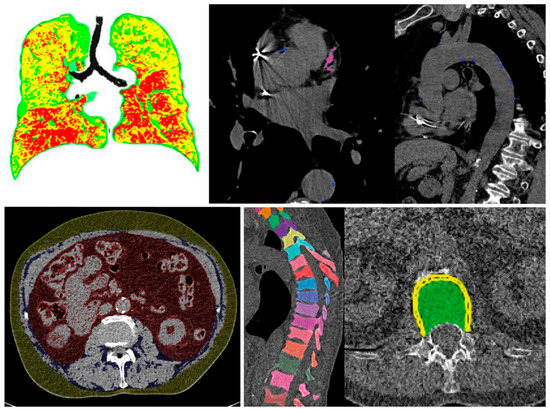

All findings resulting from the automated assessment are displayed in a structured “hAIco” (Heidelberg AI-based detection of Comorbidities) report (Figures S1 and S2). Along with the detailed quantitative information on findings, the report includes reference values if available and recommendations for additional diagnostic workup. According to the significance, findings are labelled by colors which is intended to support an intuitive report for physicians and patients. Findings with measured values beyond normal are marked in red. Green labelled results are within range. Values in between these two categories are marked yellow. Cross-sectional images are attached at the end of each report with demonstration of the organ segmentations and measurements, as well as highlighting the pathologic findings (Figure 2 and Figure 3) and the online supplementary material demonstrates the results of the comorbidity analysis of chest CT scans of two patients.

The automated evaluation of an un-enhanced chest CT scan from a 66-year-old male patient for the diagnostic workup of chronic lung disease quantified moderate parenchymal lung changes with mild signs of Emphysema, COPD and bronchial wall thickening (Figure 3, Table 3, Figure S2: COPD Patient). Additionally, this patient demonstrated an intermediate level of hepatic steatosis hepatis with an otherwise average body fat distribution. With an Agatson score >200 of CAC, this patient is expected to have a high risk of cardiac events. Hence, statin therapy is highly recommended [53,81,82,92]. BMD was significantly reduced with t-scores at osteoporotic level in need of diagnostic workup [19].

Figure 3. Example no. 2 ‘COPD patient’—Summary of organ segmentations and pathological findings from left to right and top to bottom: COPD, coronary and aortic calcifications, visceral, subcutaneous and intramuscular adipose tissue, and vertebral segmentations for assessment of BMD.